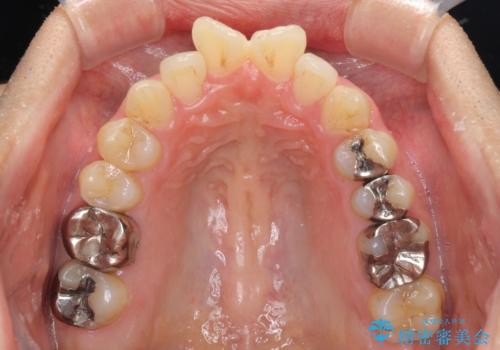

奥歯には目立つ銀歯が多くあるので、矯正治療後には下顎の銀歯をセラミッククラウンやセラミックインレーにより、補綴・修復治療することとしました。

上顎歯列全体を後方に移動させたため、口元の突出感も改善され、装置を外してからは口が閉じやすくなりました。

また、上下犬歯が接触するようになったため、奥歯にストレスのかからない歯ぎしりができるようになり、顎の疲れも改善されました。